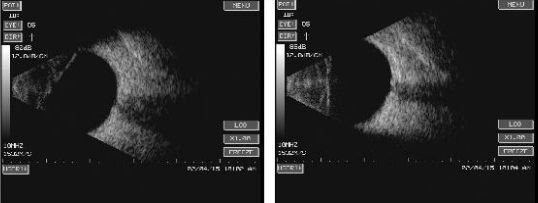

——玻璃体内可见一高回声弧形光带与球壁回声/视乳头回声相连,并渐与球壁回声融合,球壁回声与弧形光带间为无回声暗区;

——玻璃体内可见与视盘相连的漏斗形高回声光带,其与球壁回声间为无回声暗区;